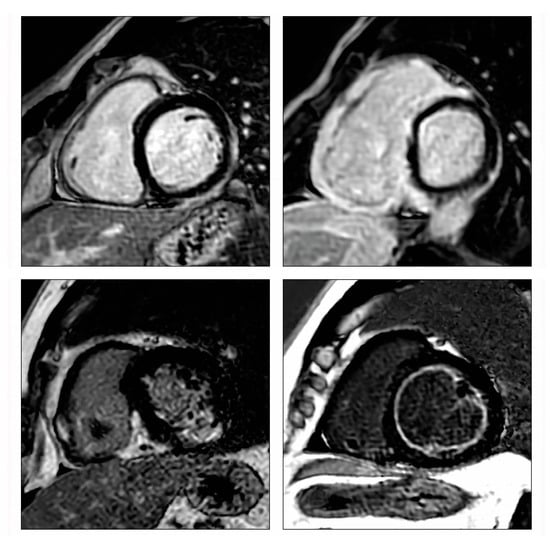

- Ferreira, V.M.; Schulz-Menger, J.; Holmvang, G.; Kramer, C.M.; Carbone, I.; Sechtem, U.; Kindermann, I.; Gutberlet, M.; Cooper, L.T.; Liu, P.; et al. Cardiovascular Magnetic Resonance in Nonischemic Myocardial Inflammation: Expert Recommendations. J. Am. Coll. Cardiol. 2018, 72, 3158–3176. [Google Scholar] [CrossRef]

- Polte, C.L.; Bobbio, E.; Bollano, E.; Bergh, N.; Polte, C.; Himmelman, J.; Lagerstrand, K.M.; Gao, S.A. Cardiovascular Magnetic Resonance in Myocarditis. Diagnostics 2022, 12, 399. [Google Scholar] [CrossRef]

- Friedrich, M.G.; Sechtem, U.; Schulz-Menger, J.; Holmvang, G.; Alakija, P.; Cooper, L.T.; White, J.A.; Abdel-Aty, H.; Gutberlet, M.; Prasad, S.; et al. Cardiovascular magnetic resonance in myocarditis: A JACC White Paper. J. Am. Coll. Cardiol. 2009, 53, 1475–1487. [Google Scholar] [CrossRef]

- Aquaro, G.D.; Perfetti, M.; Camastra, G.; Monti, L.; Dellegrottaglie, S.; Moro, C.; Pepe, A.; Todiere, G.; Lanzillo, C.; Scatteia, A.; et al. Cardiac MR With Late Gadolinium Enhancement in Acute Myocarditis with Preserved Systolic Function: ITAMY Study. J. Am. Coll. Cardiol. 2017, 70, 1977–1987. [Google Scholar] [CrossRef]

- Grani, C.; Eichhorn, C.; Biere, L.; Murthy, V.L.; Agarwal, V.; Kaneko, K.; Cuddy, S.; Aghayev, A.; Steigner, M.; Blankstein, R.; et al. Prognostic Value of Cardiac Magnetic Resonance Tissue Characterization in Risk Stratifying Patients with Suspected Myocarditis. J. Am. Coll. Cardiol. 2017, 70, 1964–1976. [Google Scholar] [CrossRef]

- Poyhonen, P.; Nordenswan, H.K.; Lehtonen, J.; Syvaranta, S.; Shenoy, C.; Kupari, M. Cardiac magnetic resonance in giant cell myocarditis: A matched comparison with cardiac sarcoidosis. Eur. Heart J. Cardiovasc. Imaging 2023, 24, 404–412. [Google Scholar] [CrossRef]

- Bobbio, E.; Bollano, E.; Oldfors, A.; Hedner, H.; Björkenstam, M.; Svedlund, S.; Karason, K.; Bergh, N.; Polte, C.L. Phenotyping of giant cell myocarditis versus cardiac sarcoidosis using cardiovascular magnetic resonance. Int. J. Cardiol. 2023, 387, 131143. [Google Scholar] [CrossRef]